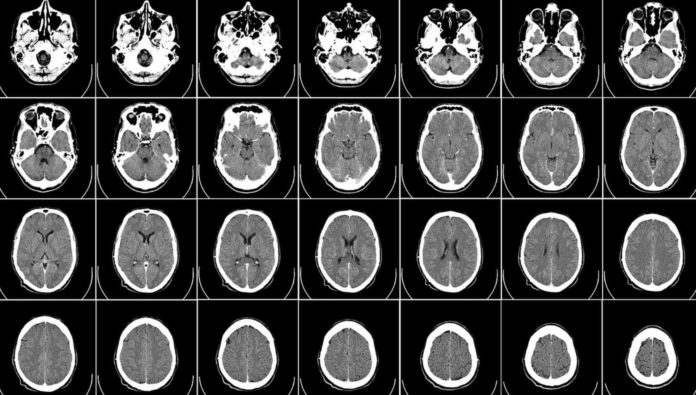

stroke

sumber: unsplash.com

Sebelum mengetahui gejala dan cara menanganinya, kita harus kenali terlebih dahulu apa itu penyakit stroke. Stroke adalah serangan pada otak yang terjadi karena adanya gangguan dalam suplai darah, yang dapat mengakibatkan kerusakan pada bagian tertentu di dalam otak.

Penyakit ini masuk ke dalam kategori darurat medis karena kerusakan dapat mengakibatkan kerja otak menjadi terganggu. Otak akan lebih sulit mendapatkan oksigen dan nutrisi, serta sel-sel otak bisa mulai mati dalam hitungan menit.